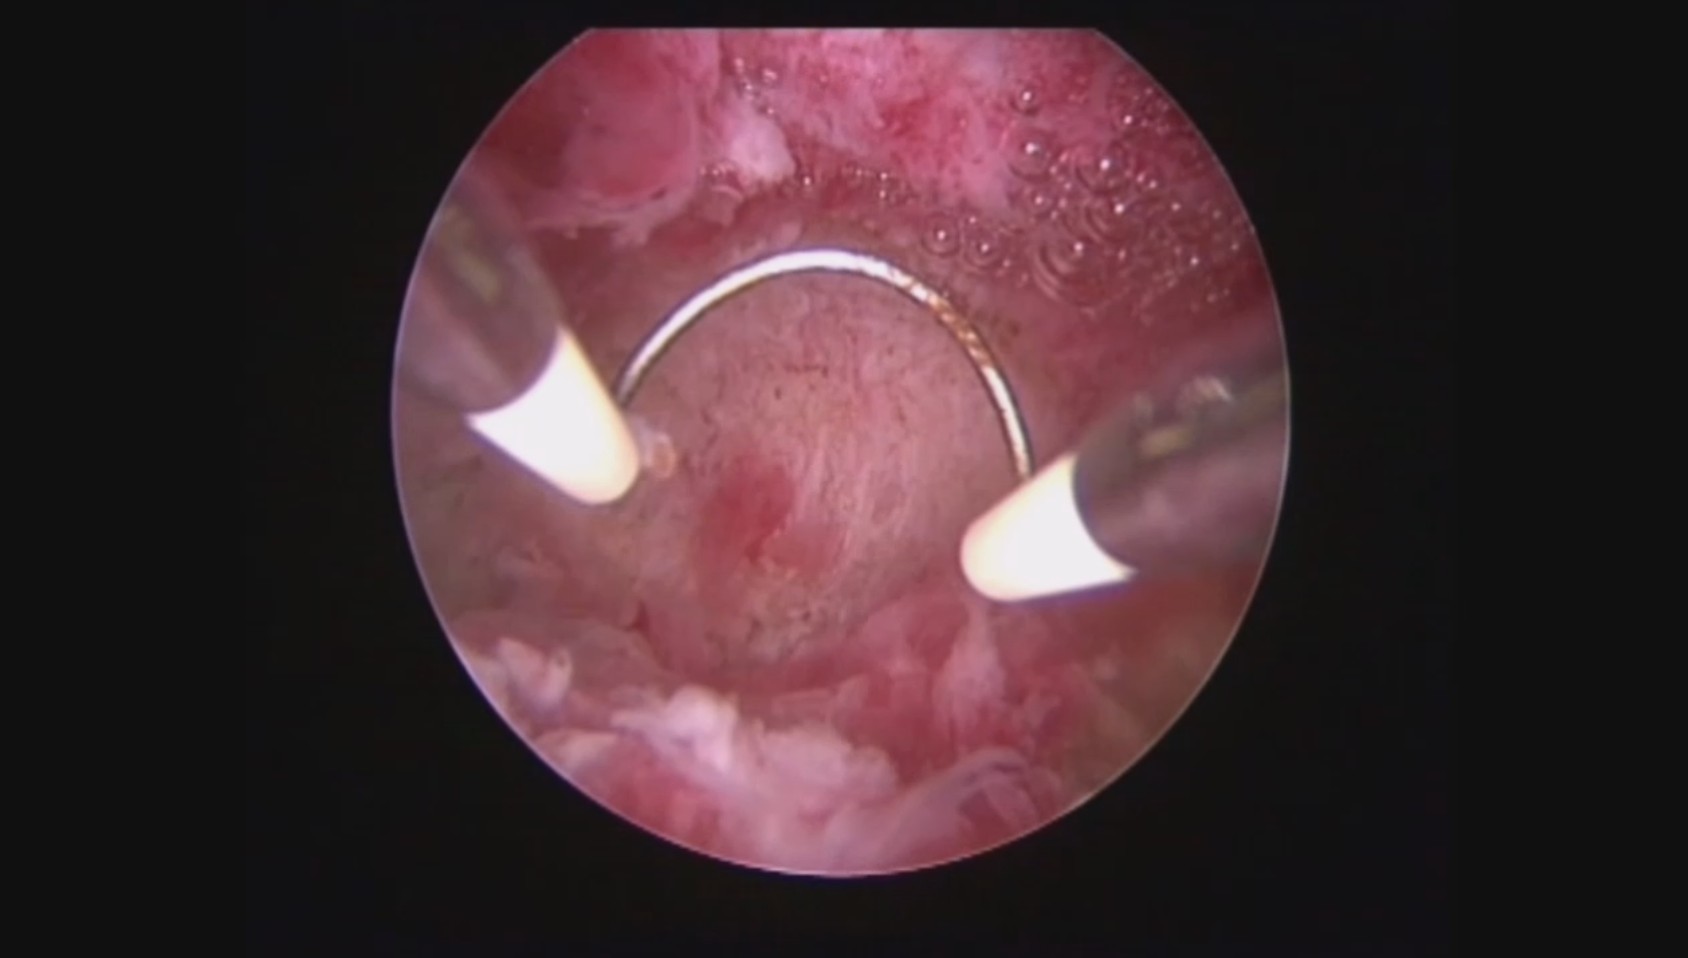

患者32岁,G6P0,继发不孕,2017年8月行宫腔镜探查,发现宫腔两侧及宫底致密粘连,尤其是宫腔右侧多重粘连,宫腔狭小。单极电切分粘,恢复宫腔形态,显露双侧输卵管开口。2018年8月自然妊娠40多天,我在兰州大学附一院生殖中心进修,病人微信发B超给我,大孕囊,胎心微弱,外院疑诊胚胎停育,拟行清宫,嘱病人不要轻易清宫,继续保胎1周,复查B超,胚胎发育正常。病人的信心和坚持成就了她自己和孩子的奇迹,孕期顺利,足月分娩。后病人再次妊娠1次,人流终止妊娠,现41岁,G8P1。